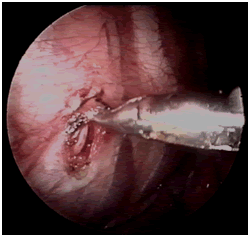

10mm鏡下右交感神經鏈全長

電刀切開胸膜,找出并切斷胸交感神經